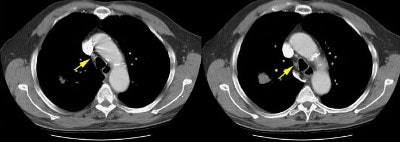

Example 1: False-positive exam -- this patient had a right upper lobe squamous-cell carcinoma. The mass is adjacent to the superior vena cava. Abnormal mediastinal N2 (yellow arrow) nodes were identified by the staging CT exam. Contralateral N3 nodes (white arrows) were borderline abnormal by size criteria. The patient underwent medianstinoscopy and anterior mediastinotomy (Chamberlain procedure) for pre-operative staging -- both of which were negative for malignant cells. The patient had underlying interstitial lung disease which has been associated with the presence of reactive mediastinal adenopathy. At surgery the patient was found to have ipsilateral hilar adenopathy (N1) and parietal pleural invasion (T3 tumor) or a stage IIIA.

Example 2: False-negative CT exam -- this patient had an adenocarcinoma in the right upper lobe that measured less than 3 cm in size (T1 lesion). The ipsilateral mediastinal nodes identified by staging CT were not pathologic by size criteria. The surgical team elected to proceed to thoracotomy without mediastinoscopy. At surgery, the small right paratracheal nodes which measured less than 1 cm where found to contain microscopic foci of tumor (N2 nodes). The patient was staged histopathologically as T1N2M0 (Stage IIIA).